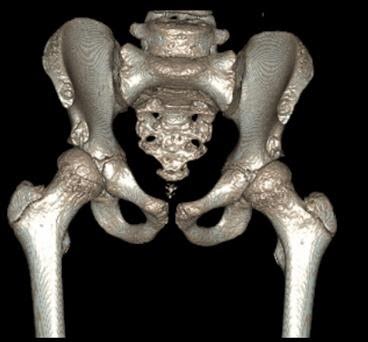

MRI demonstrated an anterior labral tear, but also lateral acetabular ‘under coverage’. The subsequent CT with 3D reconstruction images (Figs 17 & 18) – the gold standard investigation – shows dysplasia principally of the posterior wall.

Figure 17 CT (anterior view)

Figure 18 – CT (posterior view)